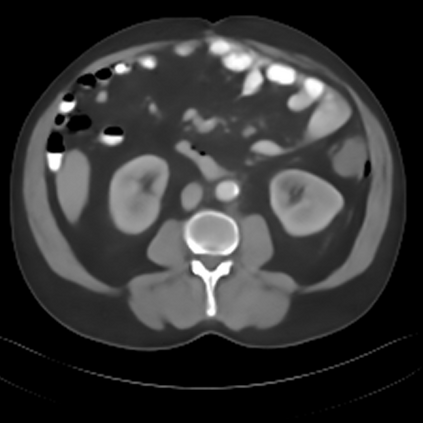

Sparse-view computed tomography (CT) -- using a small number of projections for tomographic reconstruction -- enables much lower radiation dose to patients and accelerated data acquisition. The reconstructed images, however, suffer from strong artifacts, greatly limiting their diagnostic value. Current trends for sparse-view CT turn to the raw data for better information recovery. The resultant dual-domain methods, nonetheless, suffer from secondary artifacts, especially in ultra-sparse view scenarios, and their generalization to other scanners/protocols is greatly limited. A crucial question arises: have the image post-processing methods reached the limit? Our answer is not yet. In this paper, we stick to image post-processing methods due to great flexibility and propose global representation (GloRe) distillation framework for sparse-view CT, termed GloReDi. First, we propose to learn GloRe with Fourier convolution, so each element in GloRe has an image-wide receptive field. Second, unlike methods that only use the full-view images for supervision, we propose to distill GloRe from intermediate-view reconstructed images that are readily available but not explored in previous literature. The success of GloRe distillation is attributed to two key components: representation directional distillation to align the GloRe directions, and band-pass-specific contrastive distillation to gain clinically important details. Extensive experiments demonstrate the superiority of the proposed GloReDi over the state-of-the-art methods, including dual-domain ones. The source code is available at https://github.com/longzilicart/GloReDi.